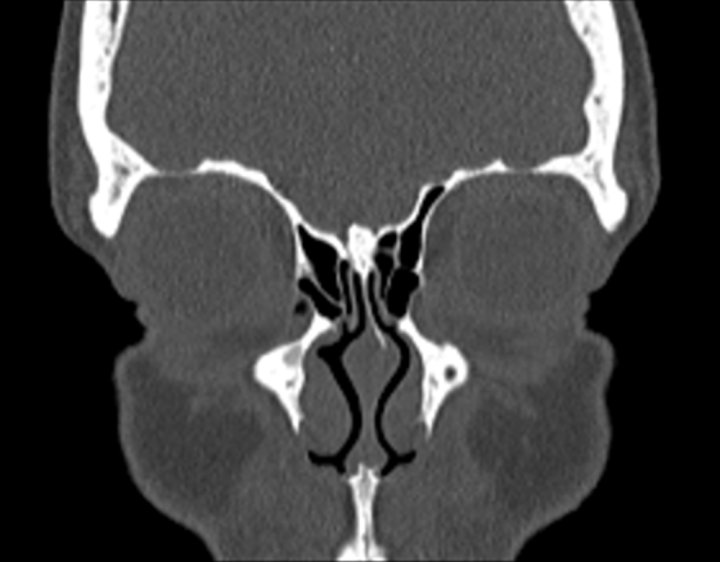

Click any image for labels.